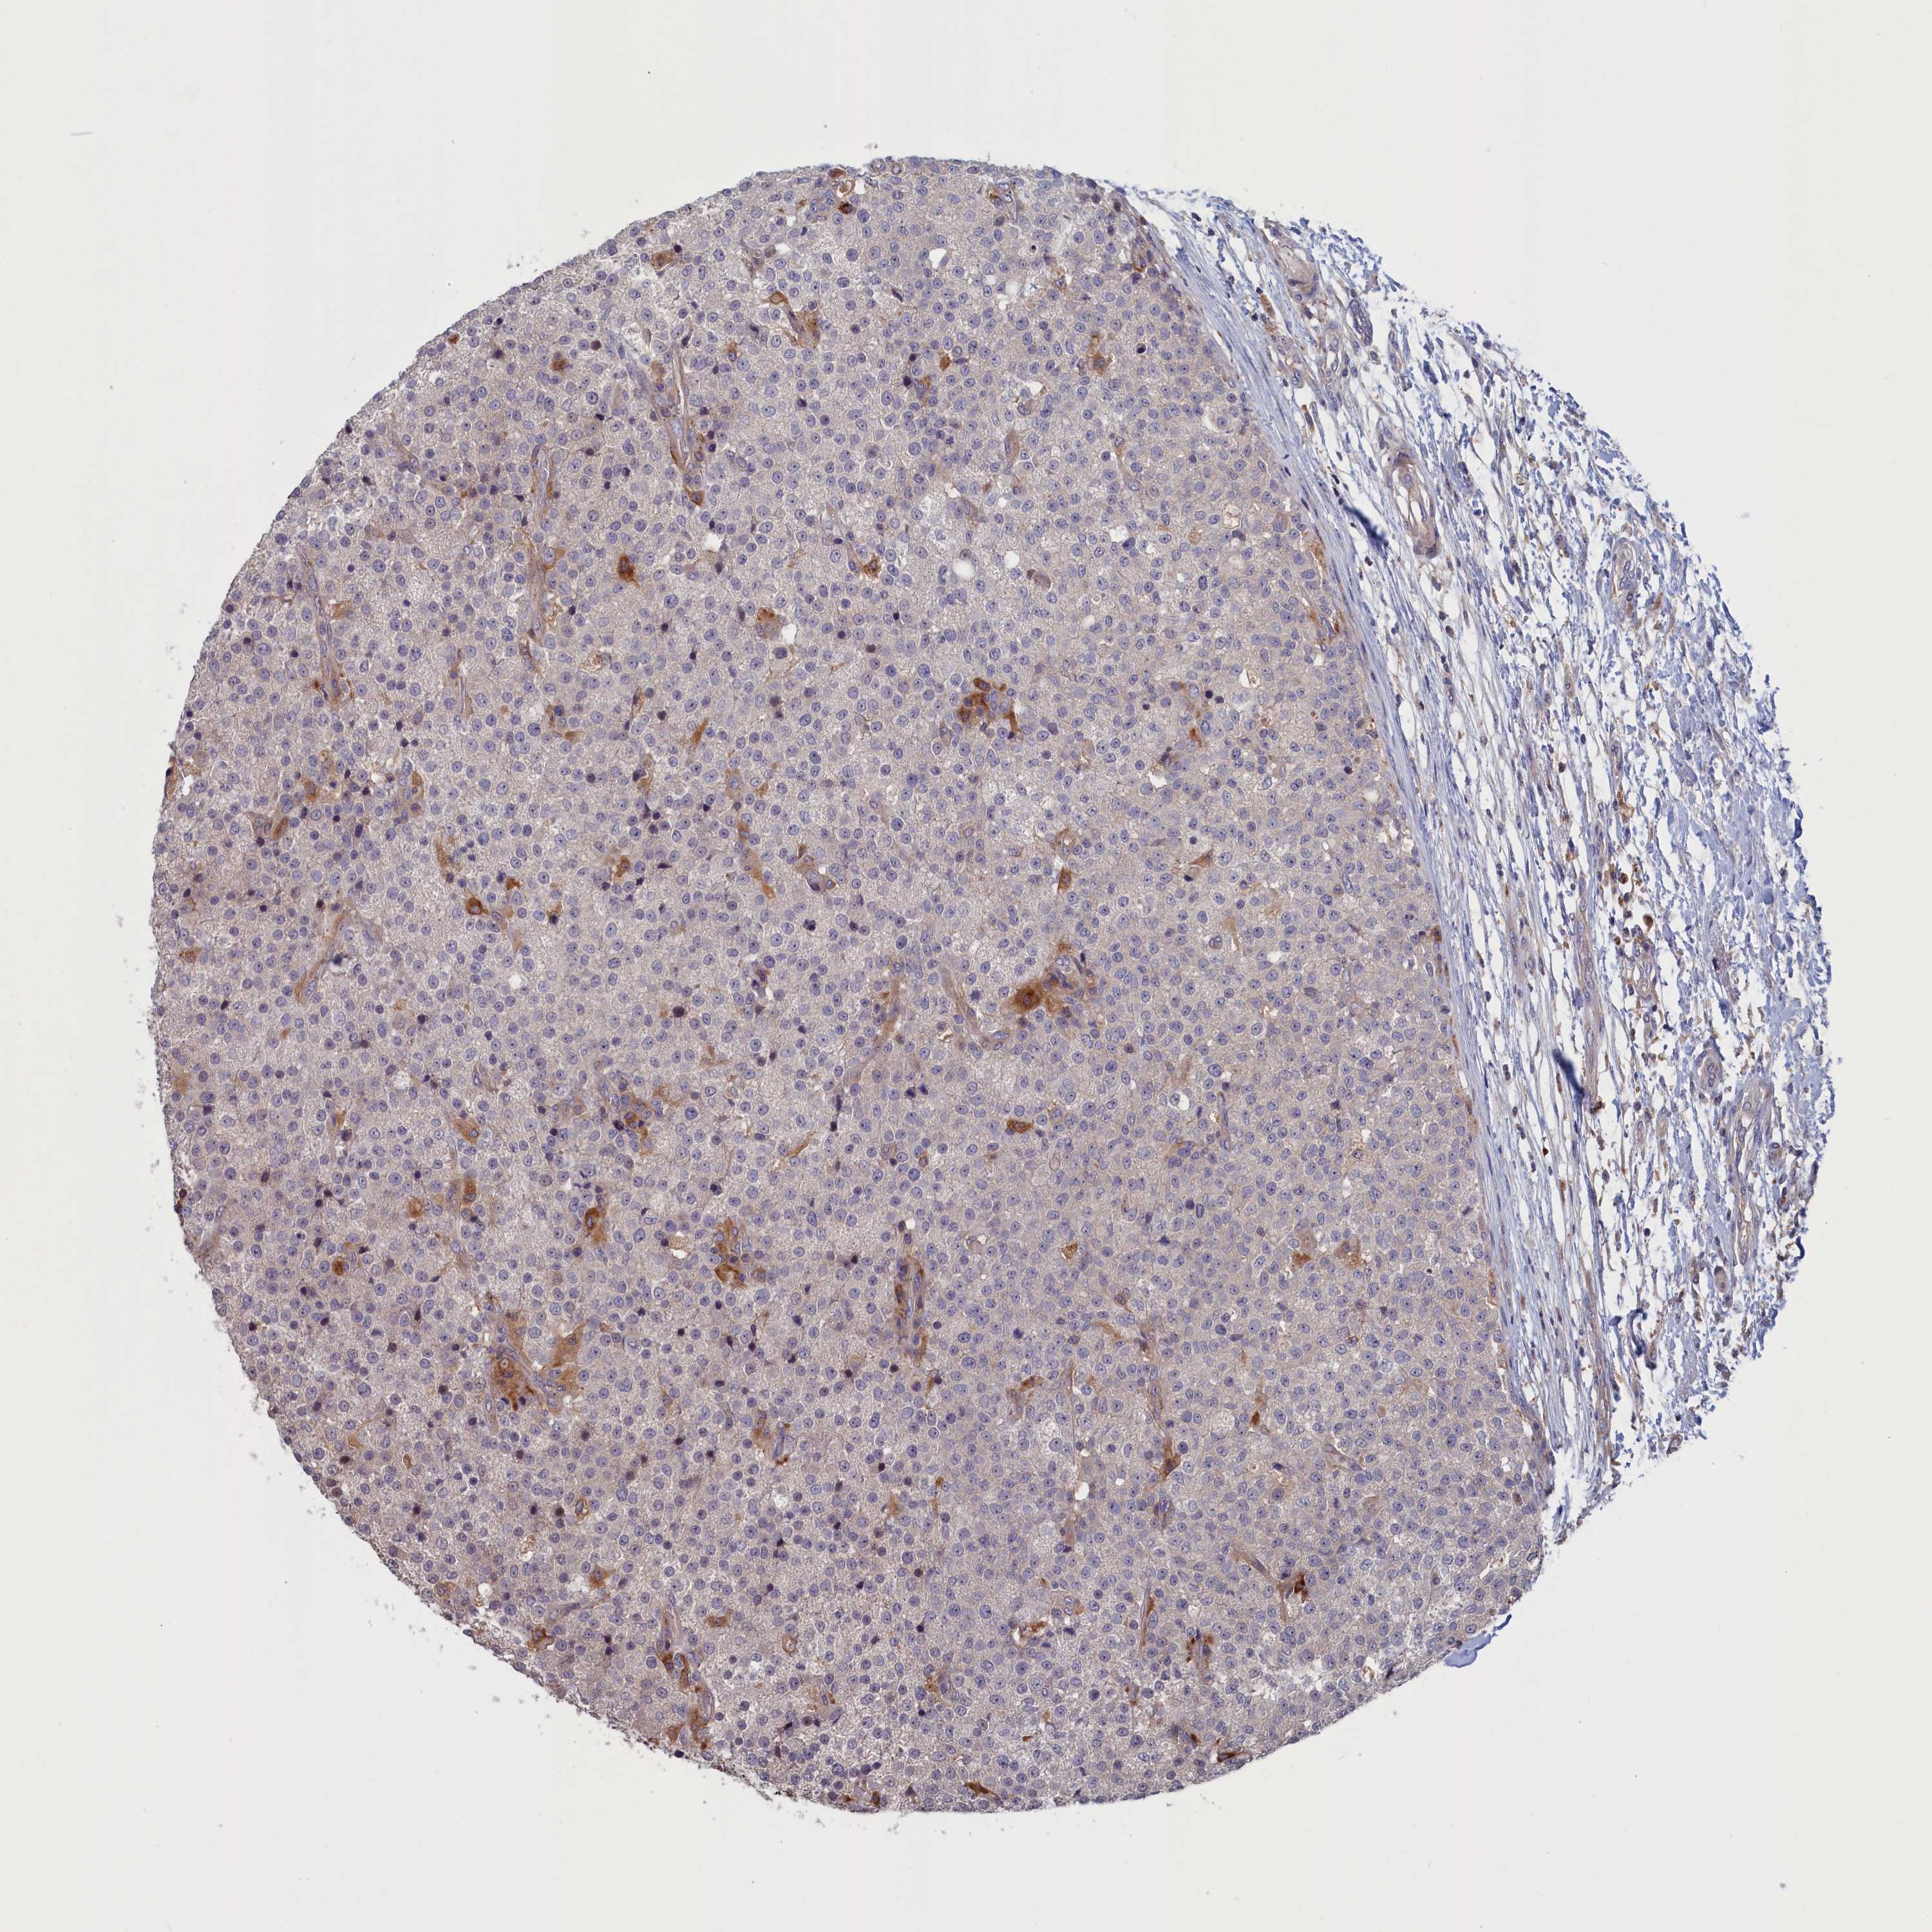

TESTIS CANCER - Protein expressioni

A mouse-over function shows sample information and annotation data. Click on an image to view it in a full screen mode. Samples can be filtered based on level of antibody staining by selecting one or several of the following categories: high, medium, low and not detected. The assay and annotation is described here.

Note that samples used for immunohistochemistry by the Human Protein Atlas do not correspond to samples in the TCGA dataset.

Antibody stainingi

Antibody staining in the annotated cell types in the current human tissue is reported as not detected, low, medium, or high, based on conventional immunohistochemistry profiling in selected tissues. This score is based on the combination of the staining intensity and fraction of stained cells.

Each image is clickable and will lead to virtual microscopy that enables deeper exploration of all samples and also displays staining intensity scores, fraction scores and subcellular localization as well as patient and tissue information for each sample.

Antibody HPA042504

Antibody HPA042548

Staining

High

Medium

Low

Not detected

Intensity

Strong

Moderate

Weak

Negative

Quantity

>75%

75%-25%

<25%

None

Location

Nuclear

Cytoplasmic/membranous

Cytoplasmic/membranous,nuclear

Carcinoma, Embryonal, NOS

Seminoma, NOS